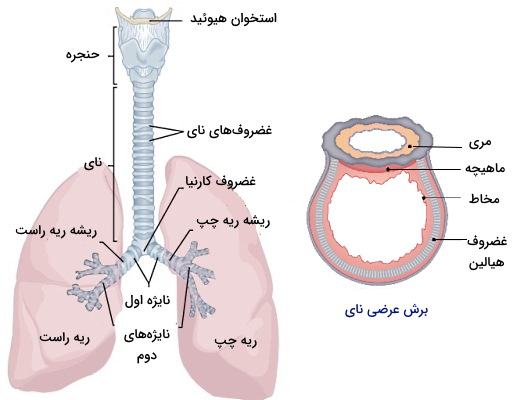

آناتومی درخت برونشیال

درخت برونشیال از مسیرهایی تشکیل شده است که هوا را به کیسههای هوایی هدایت میکنند. نای، نایژهها و نایژکها لولههای تنفسی این سیستم هستند. نای اولین بخش درخت برونشال است که از ناحیه پایینی غضروف کوریتیکوئید شروع شده و در ابتدای مدیاستوم به نايژکهای چپ و راست تقسیم میشود. مری پشت نای قرار دارد.

دیواره نای از غضروفهای C شکلی تشکیل شده است که ماهیچههای صاف بین آنها قرار میگیرند. اپیتلیوم داخلی این مجرا از نوع استوانهای مطبق کاذب و مژهدار است که سلولهای گابلت بین آنها قرار میگیرد. مخاط ترشح شده از سلولهای گابلت ذرات خارجی و پاتوژنها را به دام میاندازد و حرکت مژهها این ذرات را به سمت دهان میفرستد. غضروف «کارنیا» (Carina) در محل دو شاخه شدن نای قرار دارد و حساسترین محل تحریک انعکاس سرفه است. پیامهای حسی این بخش بهوسیله اعصاب برگشتی حنجرهای به سیستم عصبی مرکزی میرسد.

نایژه همسطح زاویه سینهای از نای جدا شده و به شاخههای کوچکتر نایژه دوم تقسیم میشوند. هر نایژه دوم هوا را به یکی از لوبهای ریه هدایت میکند. در نتیجه سه نایژه دوم در ریه راست و ۲ نایژه دوم در ریه چپ قرار دارد. قطر نایژه راست بیشتر و طول آن کمتر از نایژه چپ است. نایژه چپ از پایین قوس آئورت، جلوی آئورت سینهای و مری عبور میکند تا از هیلوم (ناف) وارد ریه چپ شود. مجموعه نایژه، رشته عصبی و سرخرگ هر ریه، ریشه ریه نام دارد. نایژههای دوم به شاخههای باریکتری نایژههای سوم تقسیم میشوند. هر نایژه سوم هوا را به یکی از ناحیههای تنفسی هدایت میکند. دیواره نایژه از غضروفهای حلقهای تشکیل شده است که ماهیچههای صاف بین آنها قرار میگیرند. اما در نایژههای دوم و سوم بافت غضروفی بسیار کاهش یافته و شکل آن شبیه غضروفهای نای است.